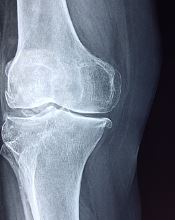

무릎 연골이 손상된 경우에는다양한 증상을 유발하며 불편함과 삶의 질에 영향을 미칠 수 있습니다. 효과적인 관리와 회복을 위해서는 이러한 증상과 해결책을 이해하는 것이 중요합니다.

무릎 연골 손상 증상

지금까지 무릎 연골 손상 증상에 대해 알아보았습니다. 연골은 한 번 손상되면 다시 재생되지 않습니다. 손상정도를 최대한 방지하는 것이 중요하고, 많이 손상되었다면 적극적으로 치료해야하고, 그 상태가 심각하다면 수술도 고려해야 합니다.